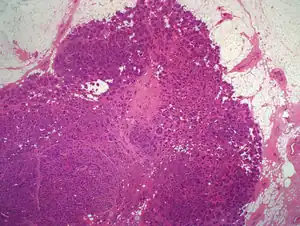

| Characteristic "jig-saw" appearance of the cylindroma present in normal breast tissue | |

A variant of eccrine spiradenoma which can be multiple on the scalp and can coalesce to form a 'Turban' tumour. In pathology, a cylindroma is a tumour with nests of cells that resemble a cylinder in cross section.